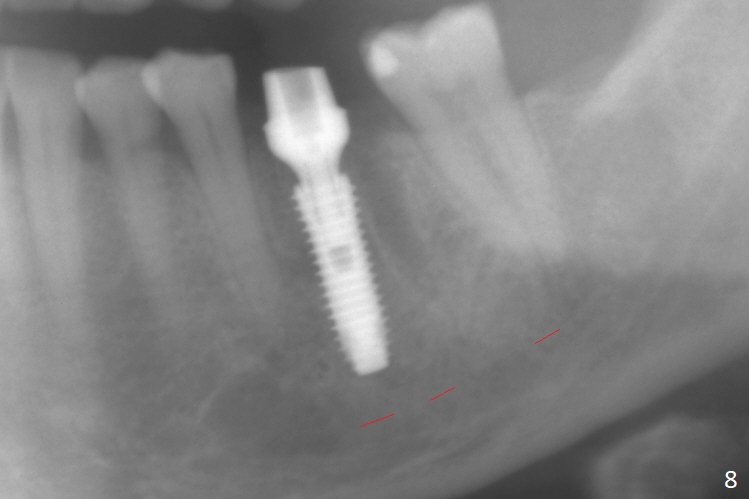

When the patient returns 9 months later, there is severe buccal gingival recession and abscess at #19 (Fig.1 *) with large mesial periradicular radiolucency (Fig.2 *). The septum is thin and the buccal crest is low after extraction (Fig.3 * (mesial root vertical fracture)). Osteotomy is initiated in the mesial socket immediately against the septum (Fig.4.5) with ~ 5 mm in the native bone. Due to severe buccal plate resorption, a shorter implant is placed (Fig.6; 5x15 mm in stead of 18 mm). There is at least 2 mm gap buccally for Vanilla Graft, which is also placed next to the implant and the neighboring root (Fig.7 *). There is clearance from the Inferior Alveolar Canal (Fig.8 red dashed line). Both the mesial and distal sockets heal 5.5 months postop (Fig.9), although the apical portion of the distal socket was not filled with allograft (Fig.7). The implant was placed mesial. The straight abutment (6.5x4(4) mm) (Fig.10) is changed to an angled one (5.5 x15 degrees 3 mm cuff (Fig.11)) before impression. The implant is also placed buccally. Therefore the implant position is far more important than its length. The abutment is retightened 2.5 months post cementation, which is related to mesiobuccal placement of the implant (Fig.12). An ideal trajectory is determined by drawing 2 horizontal lines (at crestal and apical levels: red lines in Fig.13), finding a central point of each line (vertical short line) and joining these 2 central points (Fig.14 pink line). In fact the ideal osteotomy should have been established distal to the septum in this case. Guided surgery may alleviate the issue. The crown is not loose, but the patient feels that the implant tooth cannot sustain mastication. In fact the screw is removed with hand driver (not wrench). The abutment hex is rounded and worn. A new 5.5x4(4) mm abutment is placed (without knowledge of previous use of an angled abutment) with mesial reduction to reduce undercut and buccodistal margin lowered to reduce gingival embrasure. It is that the straight abutment could decrease the chance of screw loosening. Otherwise the implant has to be removed for better trajectory.